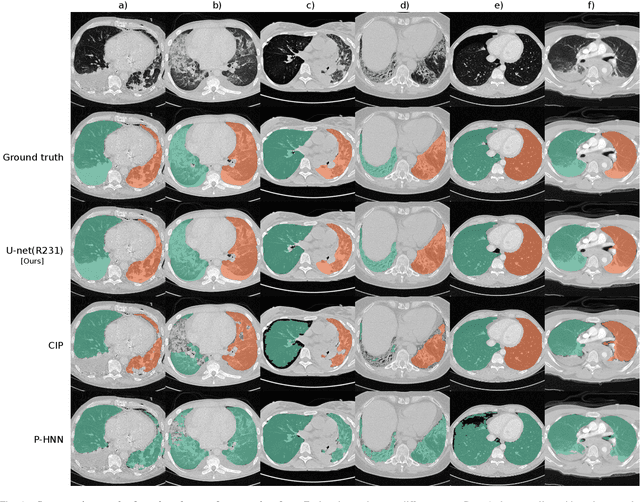

Abstract:Automated segmentation of anatomical structures is a crucial step in many medical image analysis tasks. For lung segmentation, a variety of approaches exist, involving sophisticated pipelines trained and validated on a range of different data sets. However, during translation to clinical routine the applicability of these approaches across diseases remains limited. Here, we show that the accuracy and reliability of lung segmentation algorithms on demanding cases primarily does not depend on methodology, but on the diversity of training data. We compare 4 generic deep learning approaches and 2 published lung segmentation algorithms on routine imaging data with more than 6 different disease patterns and 3 published data sets. We show that a basic approach - U-net - performs either better, or competitively with other approaches on both routine data and published data sets, and outperforms published approaches once trained on a diverse data set covering multiple diseases. Training data composition consistently has a bigger impact than algorithm choice on accuracy across test data sets. We carefully analyse the impact of data diversity, and the specifications of annotations on both training and validation sets to provide a reference for algorithms, training data, and annotation. Results on a seemingly well understood task of lung segmentation suggest the critical importance of training data diversity compared to model choice.